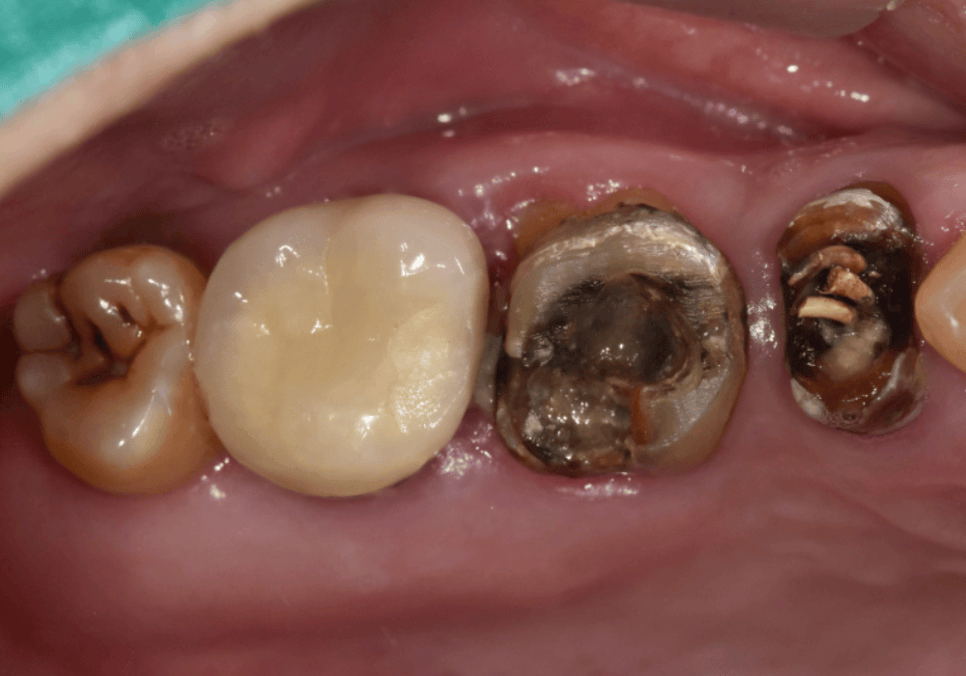

역시나.. 2차 충치로 인해 내부 치아들이

많이 삭아있는 모습인데요.

특히, 왼쪽 앞니(#21)는 충치가 너무 깊어

치아 머리 부분이 거의 남아있지 않은 상태였어요.

기둥을 세워 살리기엔 치아가

너무 약해진 상태라

결국 발치를 결정했습니다.

다행히 오른쪽 앞니(#11)는

뿌리 끝 염증이 진행 중이었지만,

흔들림도 없고 치질의 양이 꽤 남아있어서

신경치료를 통해 치아를 살려보기로 했어요.